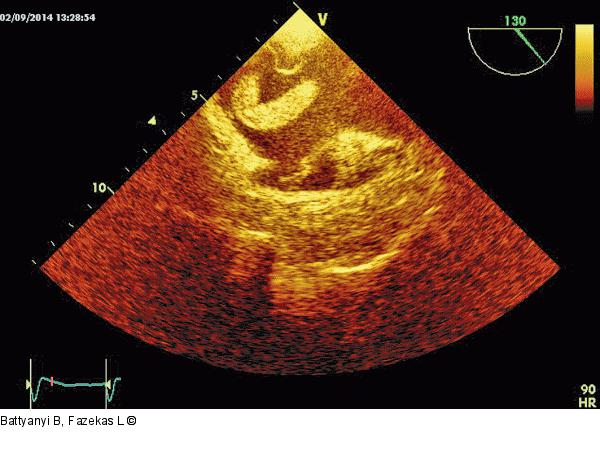

Abbildung 5: Thromboembolus

Rechter Vorhof mit dem Thromboembolus und Klappe der inferioren Hohlvene.